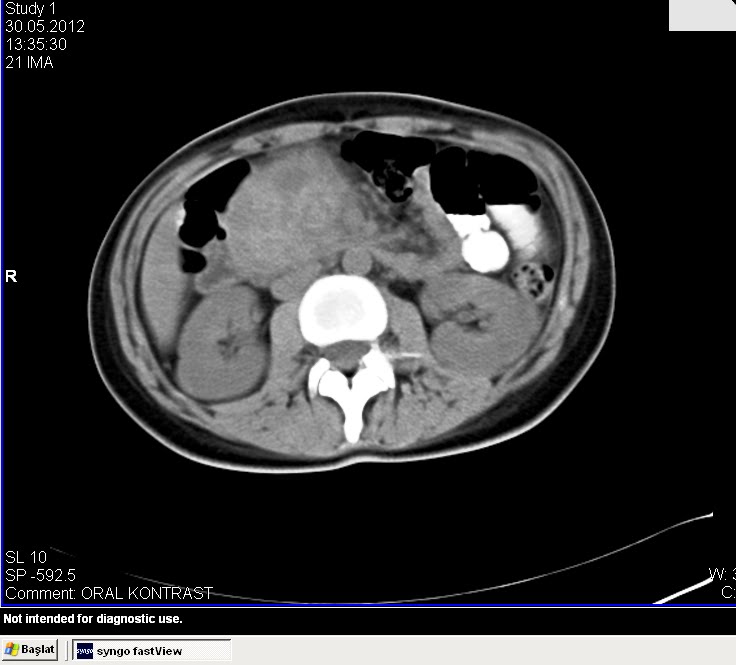

Başasistan 2012 2014 i̇stanbul türkiye. Prof dr oguzhan karatepe karaciğer safra yolları ve pankreas cerrahisi 14 aralık 2012 cuma. Pankreas kanseri ve ameliyatı prof. Oguzhan karatepe istanbul memorial şişli hastanesi genel cerrahi kliniği laparoskopik cerrahi karaciger safra yollari ve pankreas cerrahisi profilimin tamamını görüntüle.